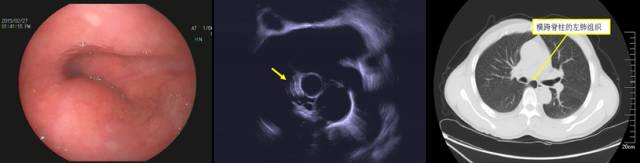

(三)肺叶外压

部分患者的右肺一叶横跨脊柱并导致食道外压性改变,超声探查同样见到的是多个平行展开的弧形气体回声。

右肺引起的食道外压( A: 内镜可见食道后壁中段隆起;B:超声发现气体回声; C:CT证实为横跨脊柱的右叶压迫所致